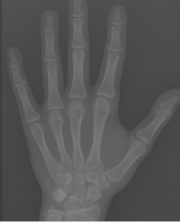

Refer to caption

Figure 1: (a) Original image. (b) Hand keypoint annotation used in BoNet [2]. (c) We convert the keypoints to bounding boxes which are used in our method to learn hand structure and extract local information.

We propose an anatomical local extraction module to learn the hand structure and extract local information for BAA. Unlike BoNet, our ALA-Net can extract the anatomical ROIs (Fig. 1) and evaluate the bone age jointly in an end-to-end manner. Benefiting from multi-task learning, the performances of anatomical region detection and BAA are significantly improved.

The original annotations of hand pose are a series of points, and we need to use boxes for local extraction. Hence, during the training time, we replace the point annotations by boxes centered at the points (Fig. 1). We use the same loss function as in [13] to train RPN, and we denote the loss function of RPN as LRPNsubscript𝐿𝑅𝑃𝑁L_{RPN}.